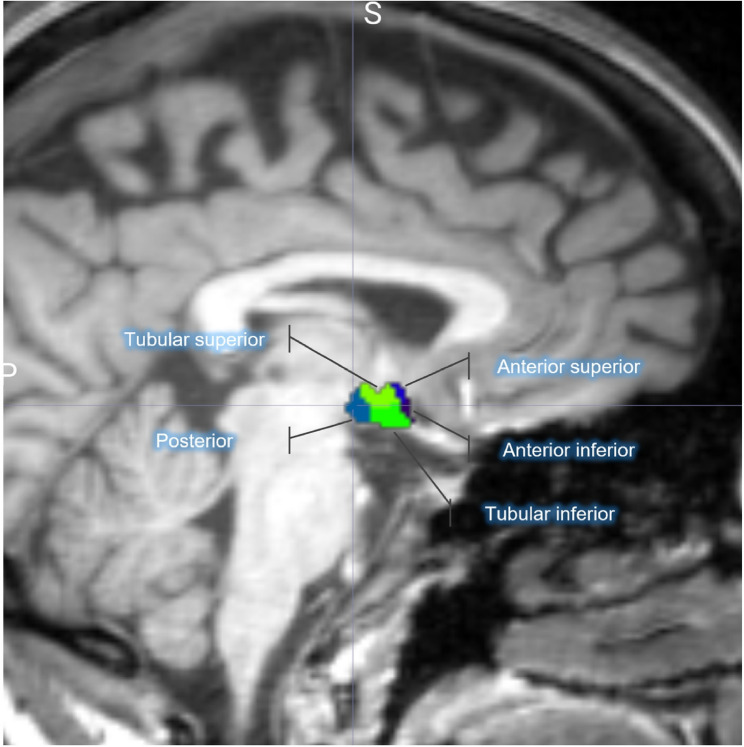

Methods: We analyzed hypothalamic volumes in 30 patients with episodic migraine without aura (MO), scanned during interictal periods and not on preventative medication, and in 30 healthy controls (HCs) matched for age and sex. Volumetric segmentation was performed of both hypothalamic subunits (anterior-inferior, anterior-superior, posterior, tubular inferior, and tubular superior) and the entire hypothalamus using magnetic resonance imaging (MRI) with T1-weighted sequences. General linear models were employed to evaluate volumetric differences after controlling for age, sex, and total brain volume.

Results: The volumes of hypothalamic subunits and overall hypothalamus volumes exhibited no statistically significant differences between HCs and MO patients (p > 0.05). No associations were found between the clinical characteristics of MO and the total hypothalamic volume or its subunits.

Conclusions: These findings suggest that the hypothalamus and its subregions do not exhibit detectable volumetric alterations during the interictal phase in patients with migraine without aura.